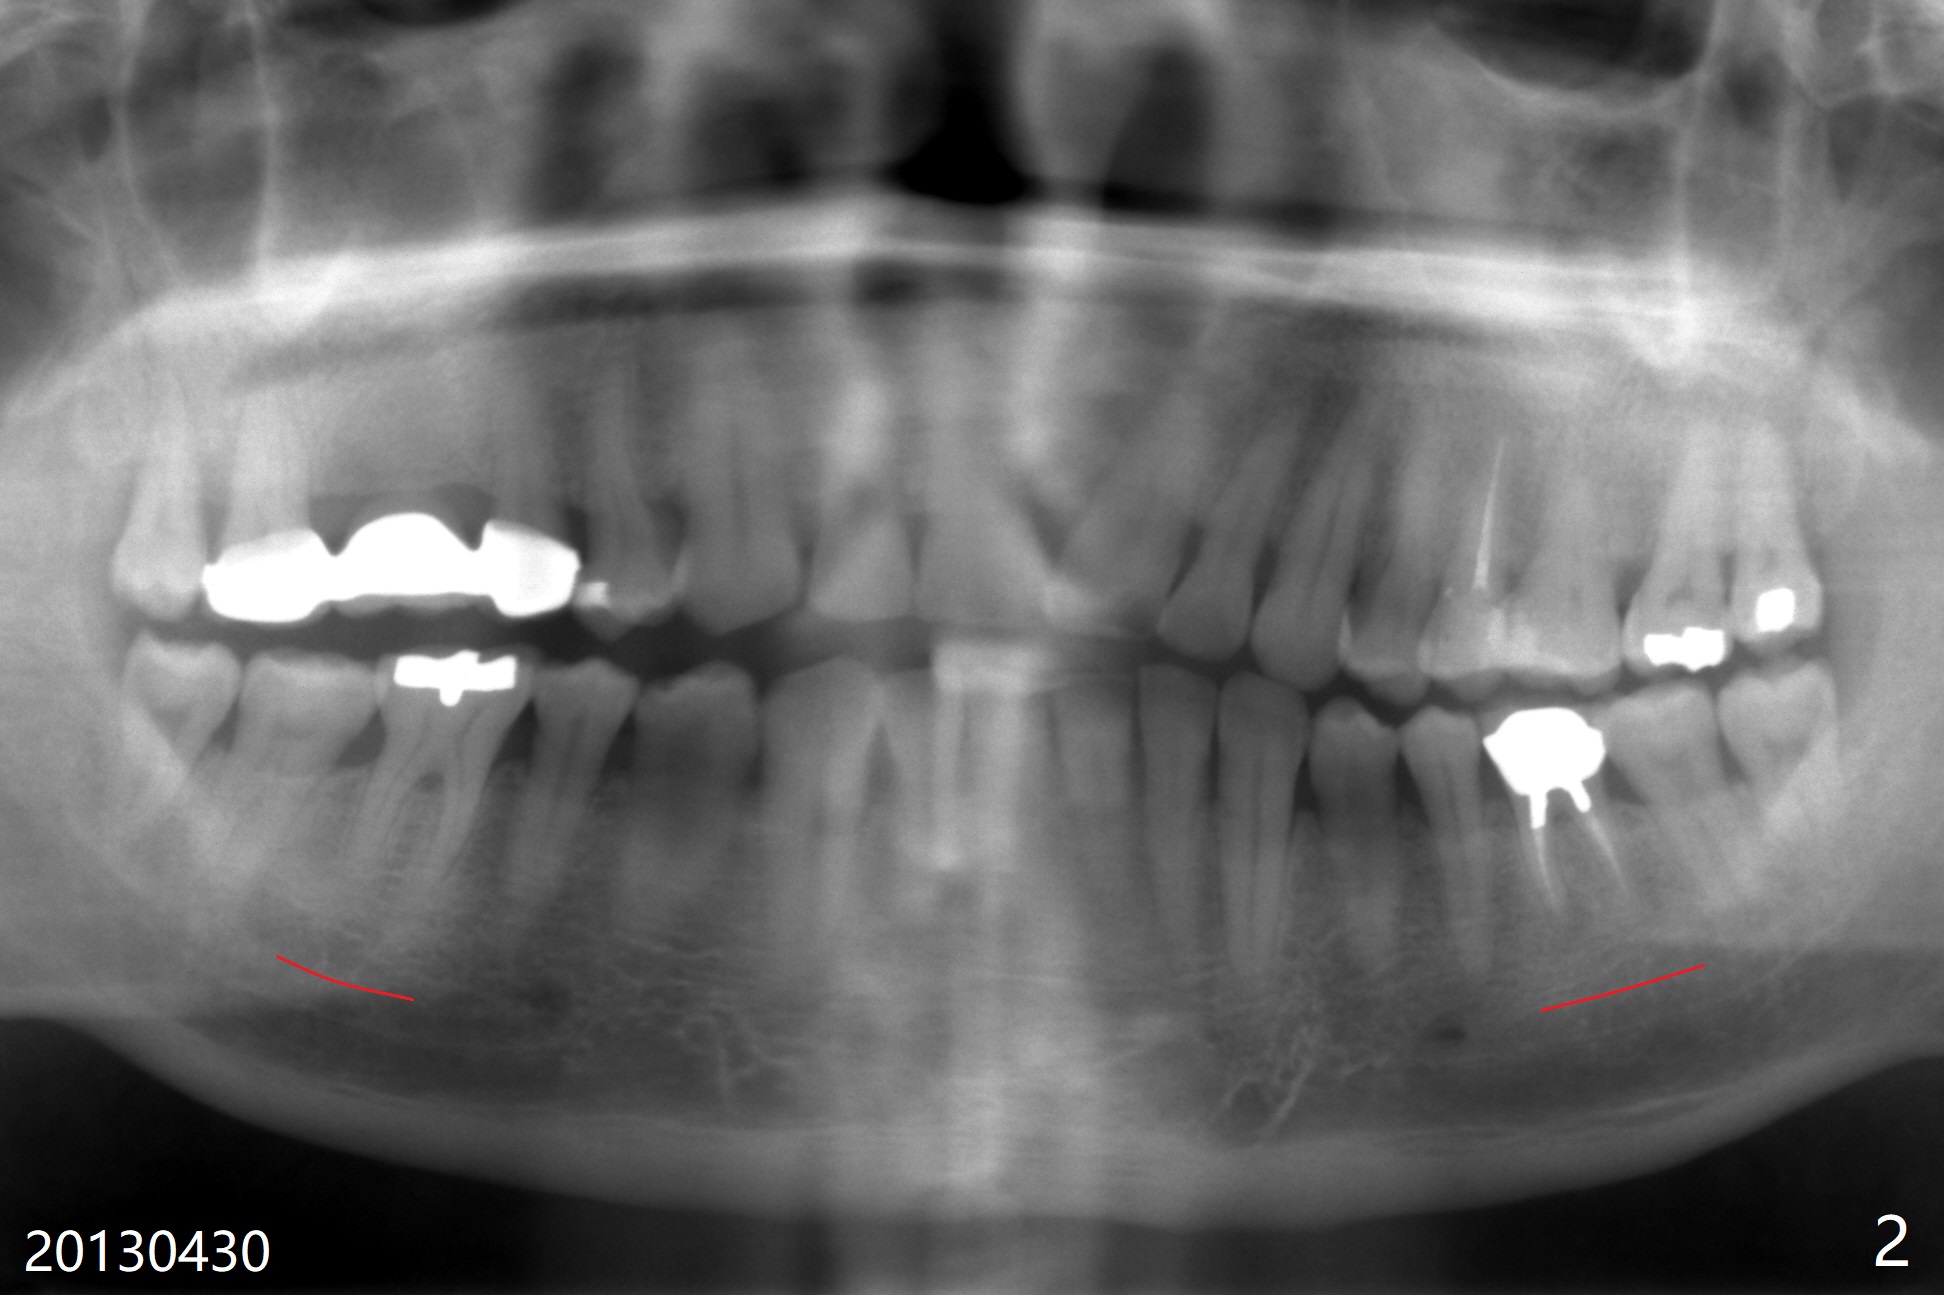

A 53-year-old man has had pain with chewing gums at #19 for 3 years (Fig.1). While a 7x17 mm implant was immediately placed at #30 six years earlier, a 5x17 mm one will be inserted at #19 as lingual as possible to reduce buccal thread exposure (Fig.2). The whole tooth will be extracted before osteotomy in the septum, since the roots in the sockets do not help free hand osteotomy unless the crown breaks off during extraction. Initial depth will be 14 mm. Use Tatum 17 mm drills. Drills are more likely deviated to the mesial socket with large PARL (Fig.1 *). Use visual acuity to correct deviation as early as possible. Pack sticky bone into the mesial bony defect for repair. Take photos of #19 and 30 for buccal recession and fistula if present. It is safe to place a 11 mm long bone level implant (Fig.3,5). It would be ideal to establish initial osteotomy as indicated by the red arrow (Fig.4).